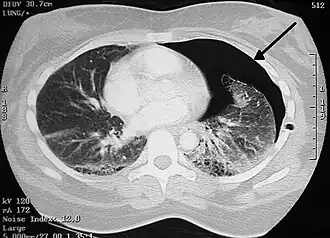

La laceración pulmonar puede no ser visible utilizando radiografía de tórax porque una contusión pulmonar asociada o hemorragia lo puede ocultar. Cuando la contusión pulmonar aclara (normalmente dentro dos a cuatro días), las laceraciones comienzan a ser visibles en la radiografía de tórax.[14] Una TAC es mejor detectando laceraciones pulmonares que una radiografía de tórax,[15] y a menudo revelan múltiples laceraciones en casos donde radiografía de pecho mostró solo un contusión. Antes de que las TAC estuvieran disponibles masivamente, la laceración pulmonar era considerada poco usual debido a que no era común encontrarlas en las radiografías. En una TAC las laceraciones pulmonares aparecen en un área contusa del pulmón,[16] típicamente apareciendo como las cavidades llenas de aire o fluido[17] que normalmente tener una forma circular u ovoide debido a la elasticidad del pulmón.